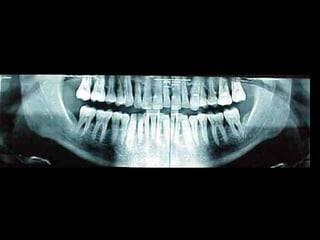

La periodontitis, denominada comúnmente piorrea, es una enfermedad que

inicialmente puede cursar con gingivitis, para luego proseguir con una pérdida de

inserción colágena, recesión gingival, e incluso la pérdida de hueso, en el caso de

no ser tratada, dejar sin soporte óseo al diente. La pérdida de dicho soporte

implica la pérdida irreparable del diente mismo.

De etiología bacteriana que afecta al periodonto (el tejido de sostén de los dientes,

constituido por la encía, el hueso alveolar, el cemento radicular y el ligamento

periodontal) se manifiesta más comúnmente en adultos mayores de 35 años, pero

puede iniciarse en edades más tempranas.

Periodontitis

•Zerón Agustín. Nueva clasificación de las enfermedades periodontales. ADM. 2001; LVIII(1):16-20.

Clasificación

Una periodontitis según su grado de afectación dental se clasifica en: leve,

moderada o grave. Y según su extensión se denomina: localizada o

generalizada.

Las periodontitis desde 1999 se han clasificado (ASP) en: crónicas,

agresivas y asociada a estados sistémicos.